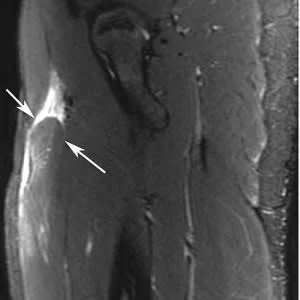

• The lower limb was the most common location of imaging-depicted sports-related injuries overall, and imaging of lower extremities was the most common exam. The second most common location was the upper limb.

Image Credit: RSNA